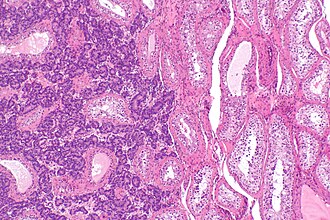

Testis with metastatic prostate carcinoma. H&E stain. (WC) | |

| LM | atypical cells between seminiferous tubules, negative for ITGCN, +/-lymphovascular invasion |

- Lack of intratubular germ cell neoplasia (ITGCN).

- Atypical cells infiltrating between benign-appearing seminiferous tubules.

- +/-Lymphovascular invasion.